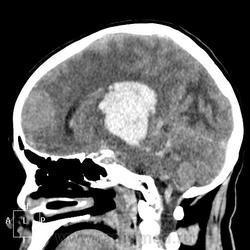

КТ головного мозга, кровоизлияние.

"Скорая" привезла женщину 75 лет, найденную на улице. На КТ направлена с д-зом: кома неясного происхождения. Вот такая картина на КТ.

Острое внутримозговое кровоизлияние с выходом крови в желудочки (боковые - сгустки преимущественно в левом + эффект седиментации с горизонтальным уровнем жидкость\жидкость в задних рогах; сгустки крови в третьем желудочке, кровь в четвертом). Значительное увеличение височных рогов боковых желудочков - гидроцефалия. Смешение срединных структур вправо, отек белого вещества перивентрикулярно слева.

Довольно большие кровоизлияния в стволе мозга (что объясняет тяжесть состояния).

Дифференциация серого и белого в-ва сохраняется, хотя субарахноидальное пространство не прослеживается - проявление масс-эффекта, начальный этап отека мозга.

Остается вопрос по слегка гиперденсному (относительно серго вещества) однородному фокусу в левой лобной доле... и по причине кровоизлияния. Что касается последнего могу предположить патологию базилярной артерии (разрыв аневризмы?)... правда не вижу что-то крови в цистернах основания черепа.

Я написала отек мозга, острое массивное (около 100 мл только внутримозговое) смешанное кровоизлияние слева + в стволе, с прорывом и гемотампонадой желудочков, выраженной латеральной дислокацией (13 мм), менингиома? лобного полюса слева. Убедительных данных за опухоль, давшую кровоизлияние, не вижу, хотя такая мысль тоже была.  Контрастировать такую пациентку никто не будет, агонизирующая(.

Массивное медиальное кровоизлияние с прорывом в желудочки. Кровоизлияние в ствол. Признаки вклинения. В лбу может что-то и есть, но это не принципиально. А может быть и отечные извилины. Смущает, что нет масс-эффекта.

Про отек: субарахноидальных щелей совсем нет, по белому веществу и в стволе снижение плотности, извилины утолщены, серое вещество на этом фоне выглядит более светлым, толстым, подушкообразным.

Причина таких кровоизлияний, как правило, гипертензия и атеросклероз.

Кровоизлияние не связанное с объемным образованием, "гипертоническое", основной массой - в области базальных ядер, кровоизлияние в ствол мозга, кома ясного происхождения :) А менингиома менигниомой, не мешает, так сказать.  Отека мозга здесь небольшой, больше выражено набухание.